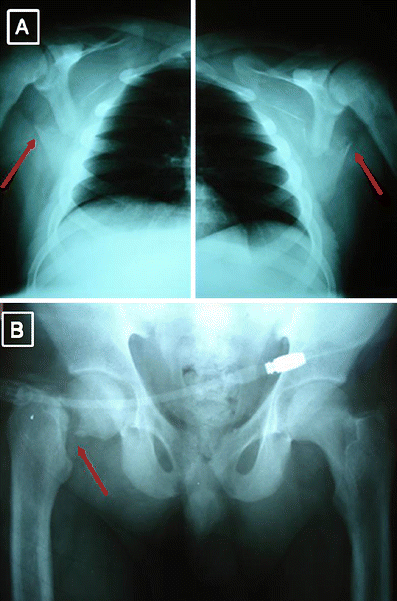

a The arrow indicates the transcervical Garden IV, Pauwels II–III right femoral neck fracture. The peritoneal lavage hose is evident. b The arrows indicate the bilateral scapular fractures

The scapular fractures were treated conservatively with analgesics and upper limb motion restriction using a collar and cuff. The hip was immobilized with a skin traction device and the patient was put on prophylactic daily dose of LMWH as well as anti-osteoporotic medication and was scheduled for operative treatment. As the patient’s general condition stabilized, 3 days later, and at the age of 19 years, he underwent a closed reduction and under fluoroscopic control, fracture stabilization with two cannulated Asnis Screws. On the third postoperative day he was allowed to walk on crutches not permitting weight bearing on the affected limb.